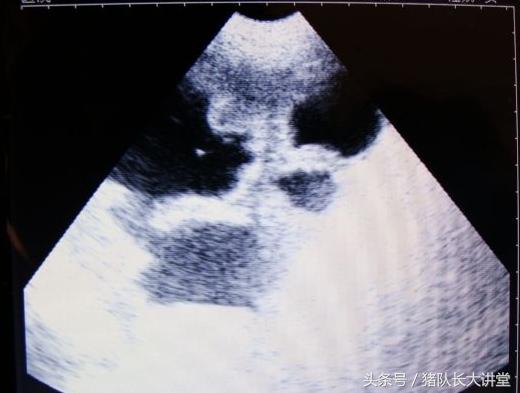

27天图

A、可以较为准确的测出是不是有小猪,具体使用办法,根据说明使用,大家也可以提出问题;注意,一般你检测有的就是有了,单是检测没有的时候应该多观察;

中间的黑球是初期胚胎